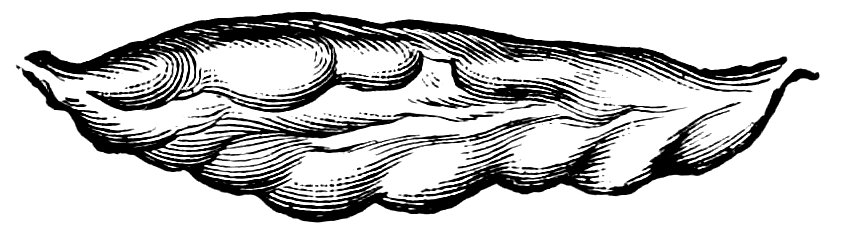

| 15. | Primitive follicles | 58 |

| 16. | Ripening follicles | 61 |

| 17. | Graafian follicles | 62 |